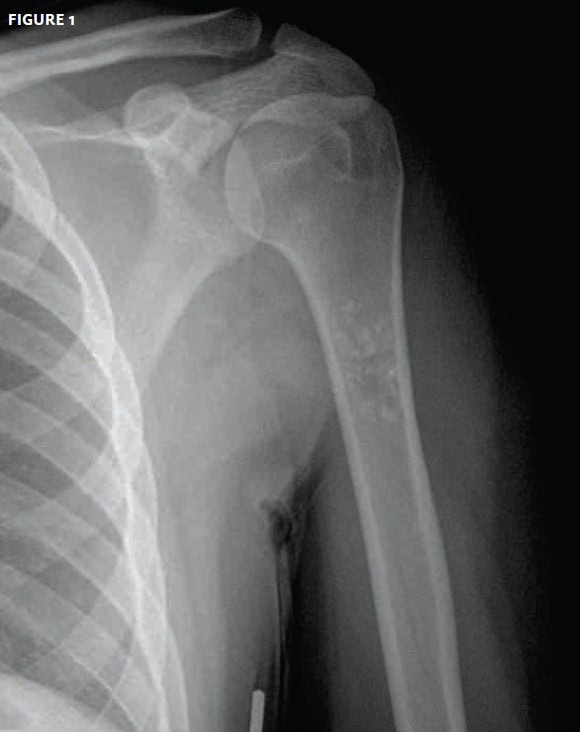

The patient, an otherwise healthy 18-yearold, presented with pain in the upper arm. There was no history of trauma.

View the image taken (Figure 1) and consider what your diagnosis and next steps would be.